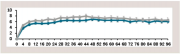

| 16:07, 16 בספטמבר 2023 | מלנומה לפי גיל.png (קובץ) |  |

36 קילו־בייטים | Motyk | 1 | |